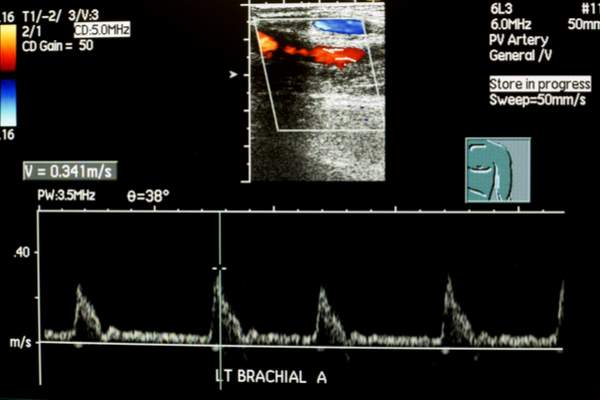

Se l’esame che ci è stato prescritto è invece l’ecocolordoppler, verremo preventivamente informati che i nostri tessuti saranno attraversati da onde ultrasonore che sfruttano l’effetto Doppler per generare una variazione di frequenza del flusso sanguigno.

Anche in questo caso l’esame non è invasivo: una tecnica di imaging avanzata permetterà al nostro terapeuta di visualizzare un diagramma dinamico della nostra frequenza sanguigna, rappresentata da una grafica a colori (blu e rosso).

In seguito, lo studio del diagramma consentirà al patologo di delineare lo stato di salute del tessuto in esame.